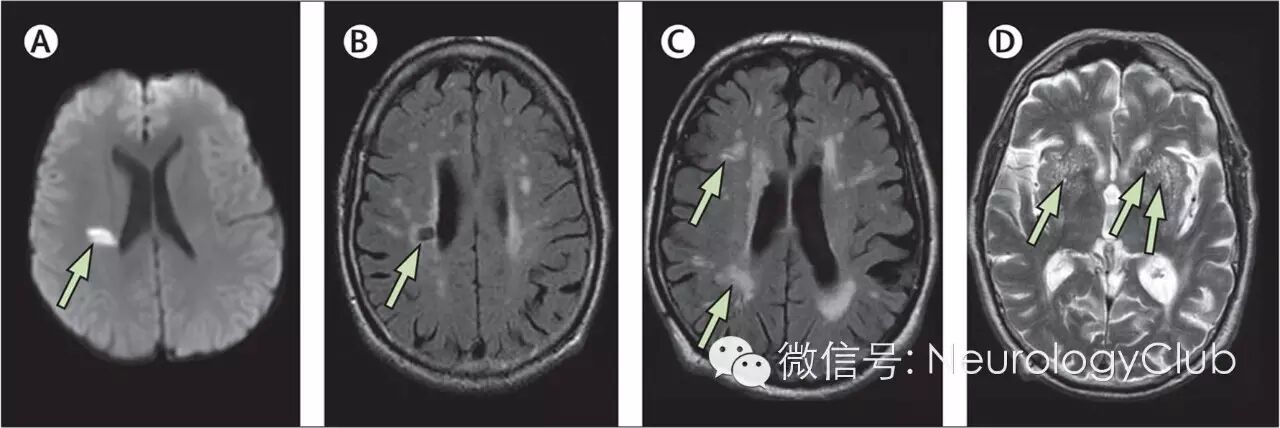

(CSVD的重要影像学特征。A:DWI提示急性深部小梗死[腔隙性梗死],直径<2cm;B:FLAIR上提示腔隙,内为脑脊液,直径在3mm-1.5cm之间,位于白质或深部灰质或者脑干,信号同脑脊液;C:FLAIR提示白质高信号,见于白质和深部灰质以及脑干,呈T2/FLAIR高信号,T1WI多不可见但偶为低信号,数量较多时可融合;D:T2WI提示血管周围间隙,因内为脑脊液样液体故而呈高信号,直径<3mm,圆形或线形,位于白质和深部灰质,明显时T1上可见低信号)

2新发皮层下小梗死

新发皮层下小梗死(recent small subcortical infarcts)常被称为腔隙性梗死(lacunar infarction,LI),MRI的弥散加权成像(diffusion weighted imaging,DWI)表现为直径3-20mm的高信号病灶。腔隙及LI主要分布于豆状核、丘脑、额叶脑白质、脑桥、基底节、内囊及尾状核。影像学所见的腔隙或LI可伴随或不伴随临床表现,不伴随临床表现则认为是“无症状性”或“静息性”,伴随临床表现时则称为腔隙综合征,常为皮质下或脑干小病变相关的特定症状及体征。

(DWI和FLAIR上不同部位形状的急性小梗死。A:内囊后肢小的卵圆形梗死;B:半卵圆中心小圆形梗死,伴白质高信号;C:内囊后肢稍大的卵圆形梗死,可见其他腔隙;D:外囊至半卵圆中心的管状梗死)